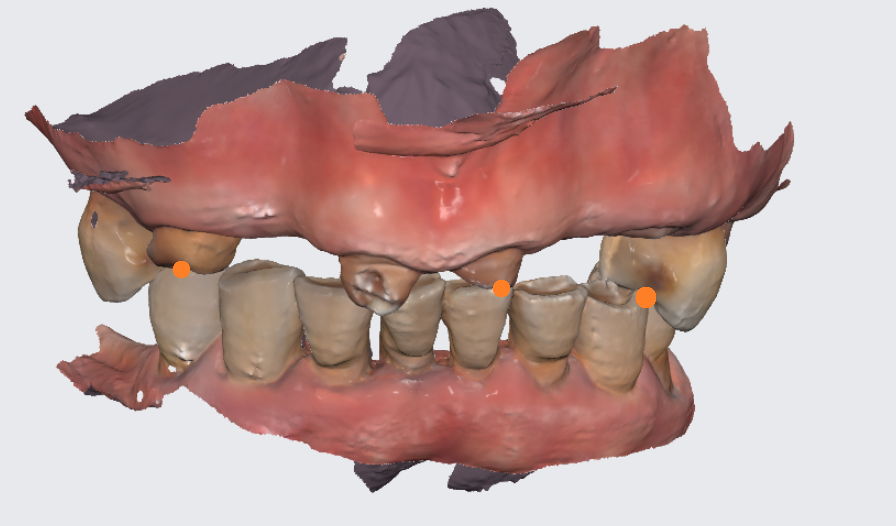

첫번째 잇몸뼈가 사라집니다.

치아가 빠졌는데 그대로 두게되면

잇몸뼈가 퇴화하게 됩니다.

얇디 얇은 종이처럼

뼈가 변하게 됩니다.

그래서 너무 늦게 오시게 되면

추석 효도선물로 임플란트를

해드리고 싶어도 못하는 경우도 생겨요ㅠㅠ